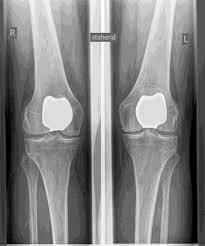

ATR (ARTICULACIÓN ARTIFICIAL DE LA RODILLA)

La articulación de rodilla artificial reemplaza la superficie del cartílago destruida por la osteoartritis. El hueso subyacente del fémur y la cabeza tibial permanece intacto. Algunos comparan una articulación artificial moderna de rodilla con la coronación de un diente; el término exacto es el llamado rejuvenecimiento bicondilar. Entre las nuevas superficies de la parte superior e inferior de la pierna se encuentra la llamada incrustación de un plástico blanco especialmente endurecido, que en la imagen de rayos X se puede ver como la distancia entre las piezas metálicas.